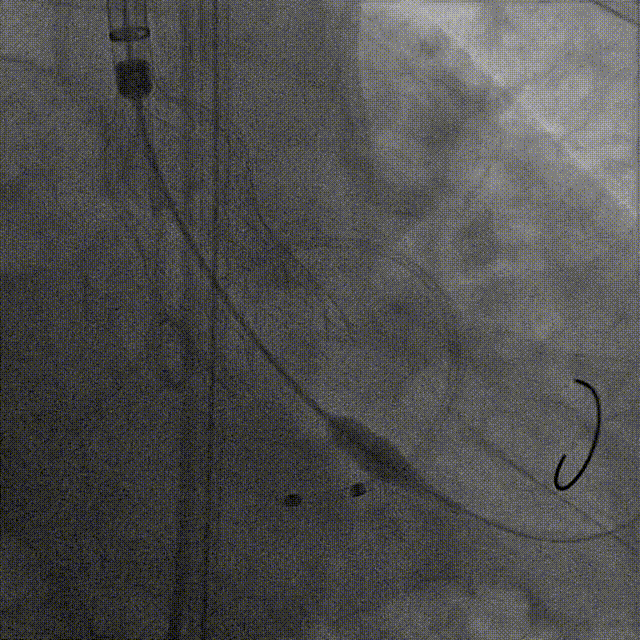

谷兴华教授 山东大学齐鲁医院 锚定终身获益,重视首次干预选择:心脏瓣膜病介入中心成立2年多来,中心核心目标始终保证在解决即刻病症的基础上,护航患者的全生命周期健康管理。 摆在眼前的实际是日益年轻化的患者群体,这意味着我们从手术伊始,就必须将患者未来数十年的生活质量和再次干预风险纳入核心考量,主动规划长远的健康路径。此次患者选择更具耐久的新型干瓣技术,力求减少患者未来再次干预的风险。同时,通过“TAVR+PCI一站式手术”这样的团队协作模式,系统性地处理多重心血管问题,避免分次手术的负担与风险,这正是我们中心一直秉持的“心脏瓣膜病全生命周期管理”理念的实践。让我们一起探索从“治已病”真正迈向“管长远”,让更多的患者获益! 病例特点速览 本次救治的患者,病情呈现“基础病交织、多病变叠加、锚定风险高”三大核心特征。患者为65岁,女性,病变特点TypeI型二叶瓣、轻度钙化,锚定风险大;同时患有冠状动脉粥样硬化性心脏病、慢阻肺(COPD);既往有长期吸烟饮酒史、脑梗死病史、高血压病史、乙肝小三阳病史及腹股沟疝修补手术史,患者STS评分9.32%,外科手术高危,经齐鲁医院瓣膜中心团队评估认为:局麻下“一站式TAVR+PCI”为最优治疗方案,结合患者较年轻,可选择具有长期耐久性的干瓣。 患者病史 主诉:活动后胸闷、憋喘余,加重20余天 既往史:30年前确诊乙肝小三阳,否认其他传染病史;有右腹股沟疝修补手术史,高血压病史,近期规律服药控制。 现病史:患者1年前出现活动后胸闷、憋喘,休息可缓解,为进一步诊治。2月前因“突发意识模糊、口齿不清”于当地医院入院,诊断为“急性脑梗死”,予以微创介入取栓治疗,恢复可,未遗留后遗症。20天前于当地医院再次入院行脑血管支架植入术,术后出现胸闷、憋喘,伴大汗,行心脏超声提示主动脉瓣重度狭窄,并行冠脉造影检查,予以药物治疗。10天前就诊于我院复查心脏超声提示二叶式主动脉瓣,主动脉瓣狭窄(重度)并反流(轻度)。患者现仍感胸闷,双上臂疼痛不适,咳嗽咳痰,日常活动受限。为行进一步治疗就诊于我院,门诊以“主动脉瓣狭窄、冠状动脉粥样硬化性心脏病”收入院; 个人史:吸烟50年,饮酒50年; 体格检查:体温:36℃,脉搏:67次/分,呼吸:18次/分,血压:143/76mmHg; 术前超声提示: 二叶式主动脉瓣主动脉瓣狭窄(重度)并反流(轻度);升主动脉扩张、左心扩大三尖瓣反流(少量);左室充盈异常;CW测最大压差86mmHg,平均压差43mmHg,最大血流速度463cm/s,连续方程法估测主动脉瓣口面积0.78cm² 术前CT评估 Type1型二叶瓣,轻度钙化、左右融合,主动脉瓣环径25.3mm,LVOT直径25.5mm,鱼嘴空间约26.6mm,主要靠瓣环锚定。窦部空间大、左右融合,VTC空间足够,无冠脉风险 ;左室内径正常,主动脉瓣环水平夹角49.6°。外周双侧入路内径可,髂外动脉存在散在钙化、双侧入路能够支持20F大鞘通过,右股低分叉,主动脉弓距弓角可。 个性化手术策略:局麻一站式方案+创新瓣膜精准适配 入路选择:主入路:右侧股动脉(右股分叉上方1cm处穿刺);辅入路:左侧股动脉;器械:20F大鞘; 手术流程规划:局麻下行同期一站式TAVR+PCI,植入ProStyle A®预装干瓣; 瓣膜选型与预处理:瓣膜型号:ProStyle A® AV32;不预扩; 定位与释放方案:初始定位:瓣上3mm处释放,瓣膜自然下滑至工作位,最终目标“0-瓣下5mm位”。 手术过程:局麻一站式操作+创新瓣膜植入,无缝衔接 手术团队按预设方案稳步推进,实现TAVR、PCI与ProStyle A®干瓣植入的无缝衔接: 1.术前准备:完成影像评估、血管通路建立,确认ProStyle A® AV32瓣膜状态; 2.PCI治疗:通过主入路完成左冠造影,前降支、对角支明显狭窄,精准植入两枚支架,恢复冠脉血供; 左冠造影,前降支、对角支病变 PCI后造影,病变血管充盈良好 3.主动脉根部造影:确认主动脉根部解剖结构,并精准跨瓣; 主动脉根部造影 精准跨瓣 4.干瓣植入:将瓣膜输送过弓、过瓣,并精准定位; 输送系统柔顺过弓 精准定位 5.术中评估:释放瓣膜至工作状态,再次造影评估,位置满意,完全释放瓣膜; 工作位评估 32号瓣膜稳定脱钩 6.释放后造影:可见瓣膜位置满意、形态良好,无明显瓣周漏。 最终造影,位置形态良好,无瓣周漏 术后超声探查:位置(瓣下4mm)、形态良好,无瓣周漏,PGmean=10mmHg。 此次手术的成功,体现了山东大学齐鲁医院心脏瓣膜病介入中心秉承的“心脏瓣膜病全生命周期管理”的理念和团队协作的临床能力。面对低龄高风险复杂病例,团队通过术前充分评估、术中精细操作,结合具有长期耐久性的干瓣技术,以一站式方案改善患者症状、提高生活质量并延长寿命,为类似病例的诊疗提供宝贵经验。 专家简介 谷兴华 山东大学齐鲁医院(点击查看专家详细简历)